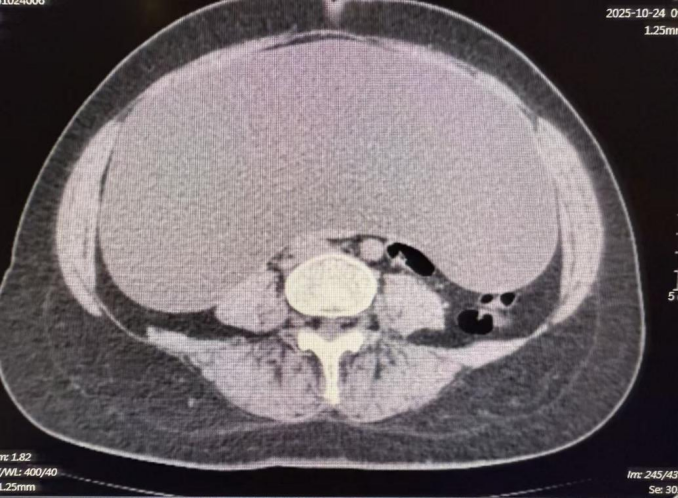

患者因发现腹腔内巨大占位性病变来到济南南郊医院就诊。术前的影像学检查结果令人震惊:腹腔内可见一范围约45cm×35cm×14cm的巨大囊性低密度影,几乎填满了整个腹腔空间,对周围脏器形成了明显的压迫。如此巨大的囊肿,不仅给患者带来了沉重的生理负担和心理压力,也对手术团队提出了极高的技术要求——如何在有限的操作空间内安全、完整地切除囊肿,同时避免损伤周围重要组织和血管,是摆在医生面前的首要难题。